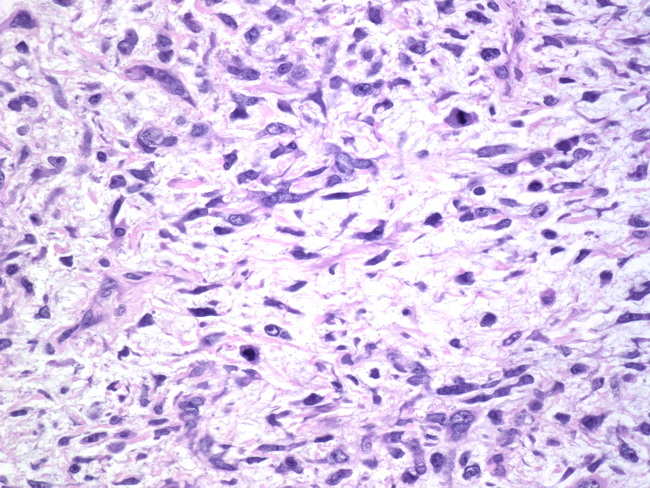

Webpathology.com: A Collection Of Surgical Pathology Images

www.webpathology.com

www.webpathology.com

leiomyosarcoma uterus myxoid pathology webpathology comments

Webpathology.com: A Collection Of Surgical Pathology Images

www.webpathology.com

www.webpathology.com

leiomyosarcoma uterus myxoid pathology webpathology stroma comments

Webpathology.com: A Collection Of Surgical Pathology Images

www.webpathology.com

www.webpathology.com

uterus leiomyosarcoma myxoid webpathology multinucleated